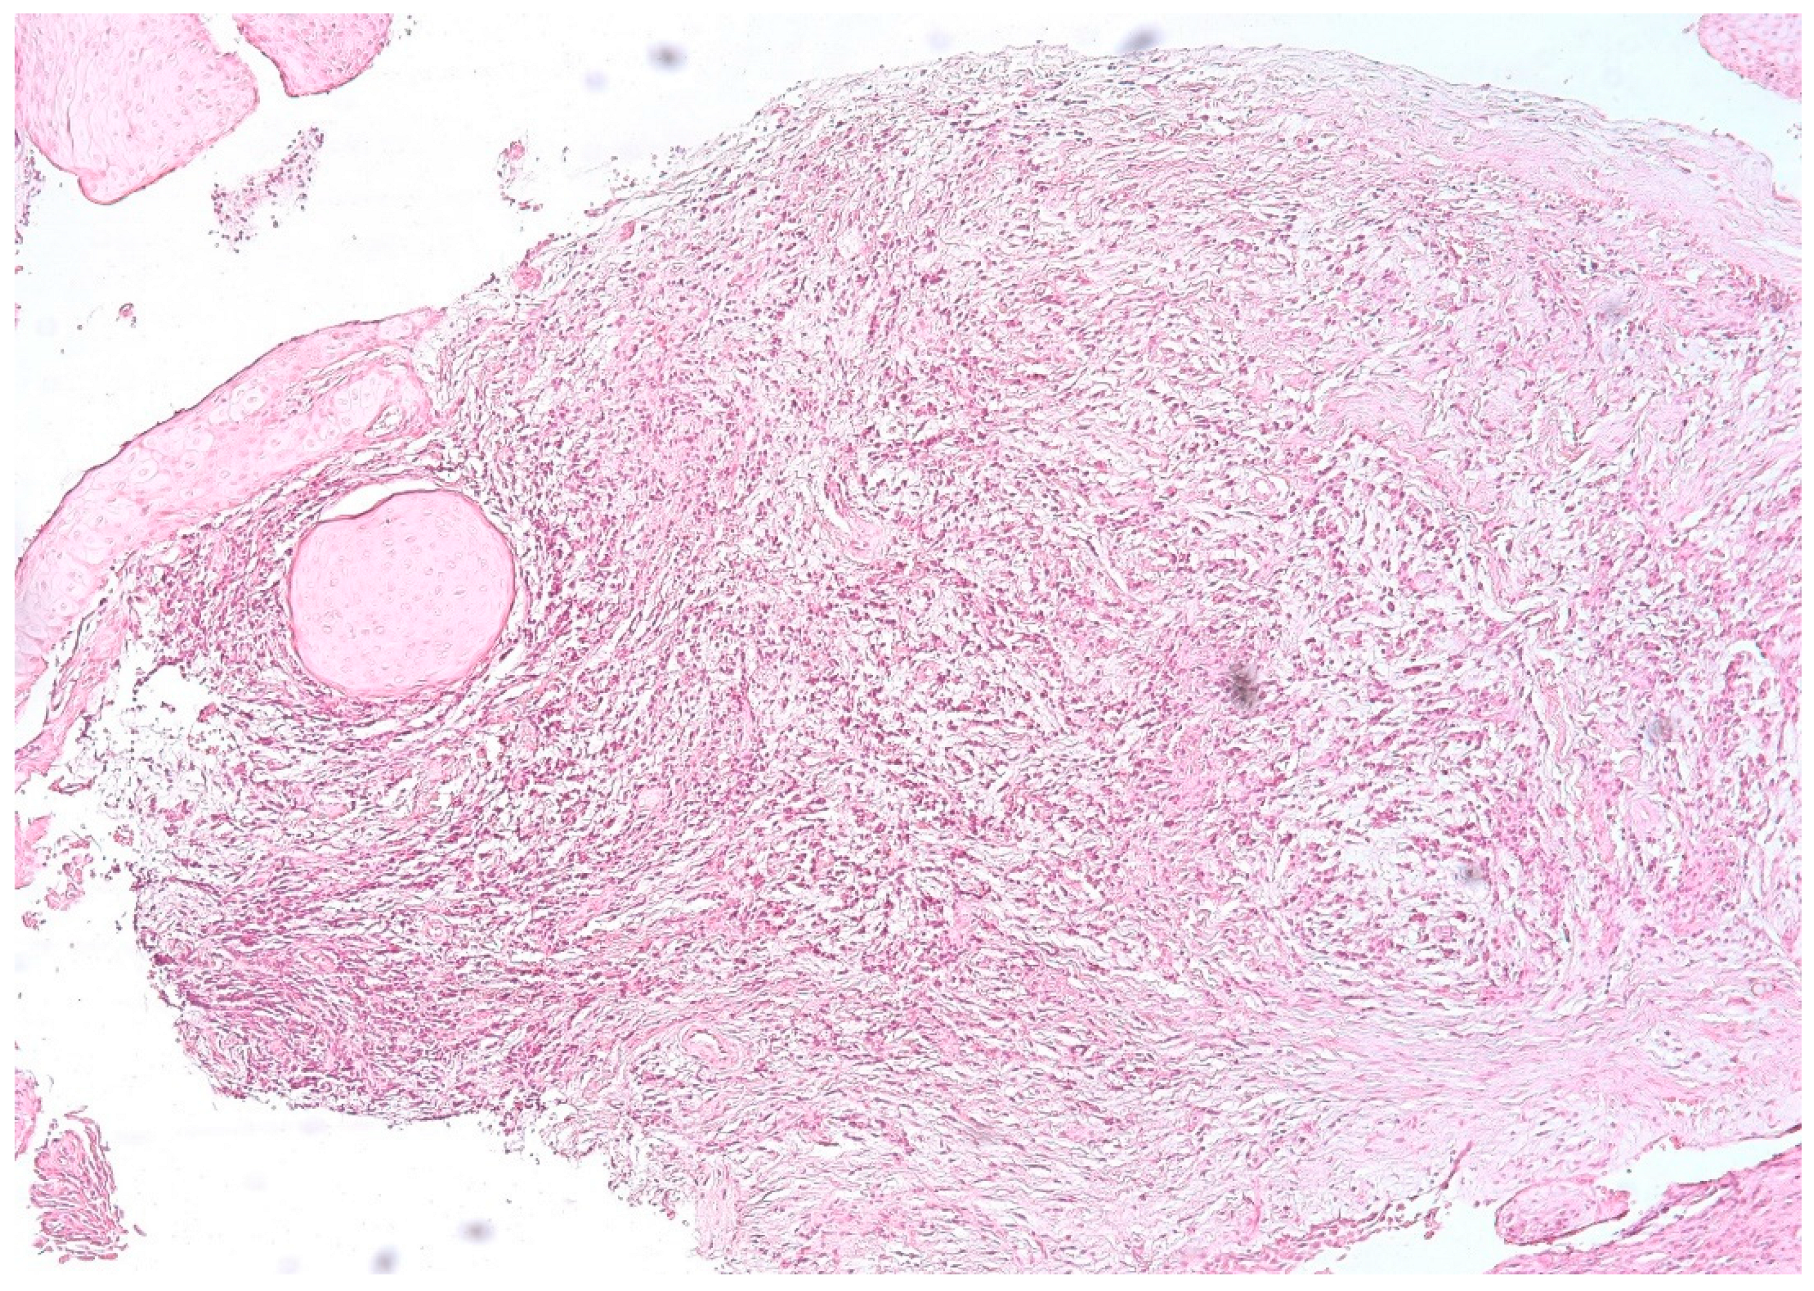

3.1. Morphologic Analysis

3.3. Aspects of Microvessels